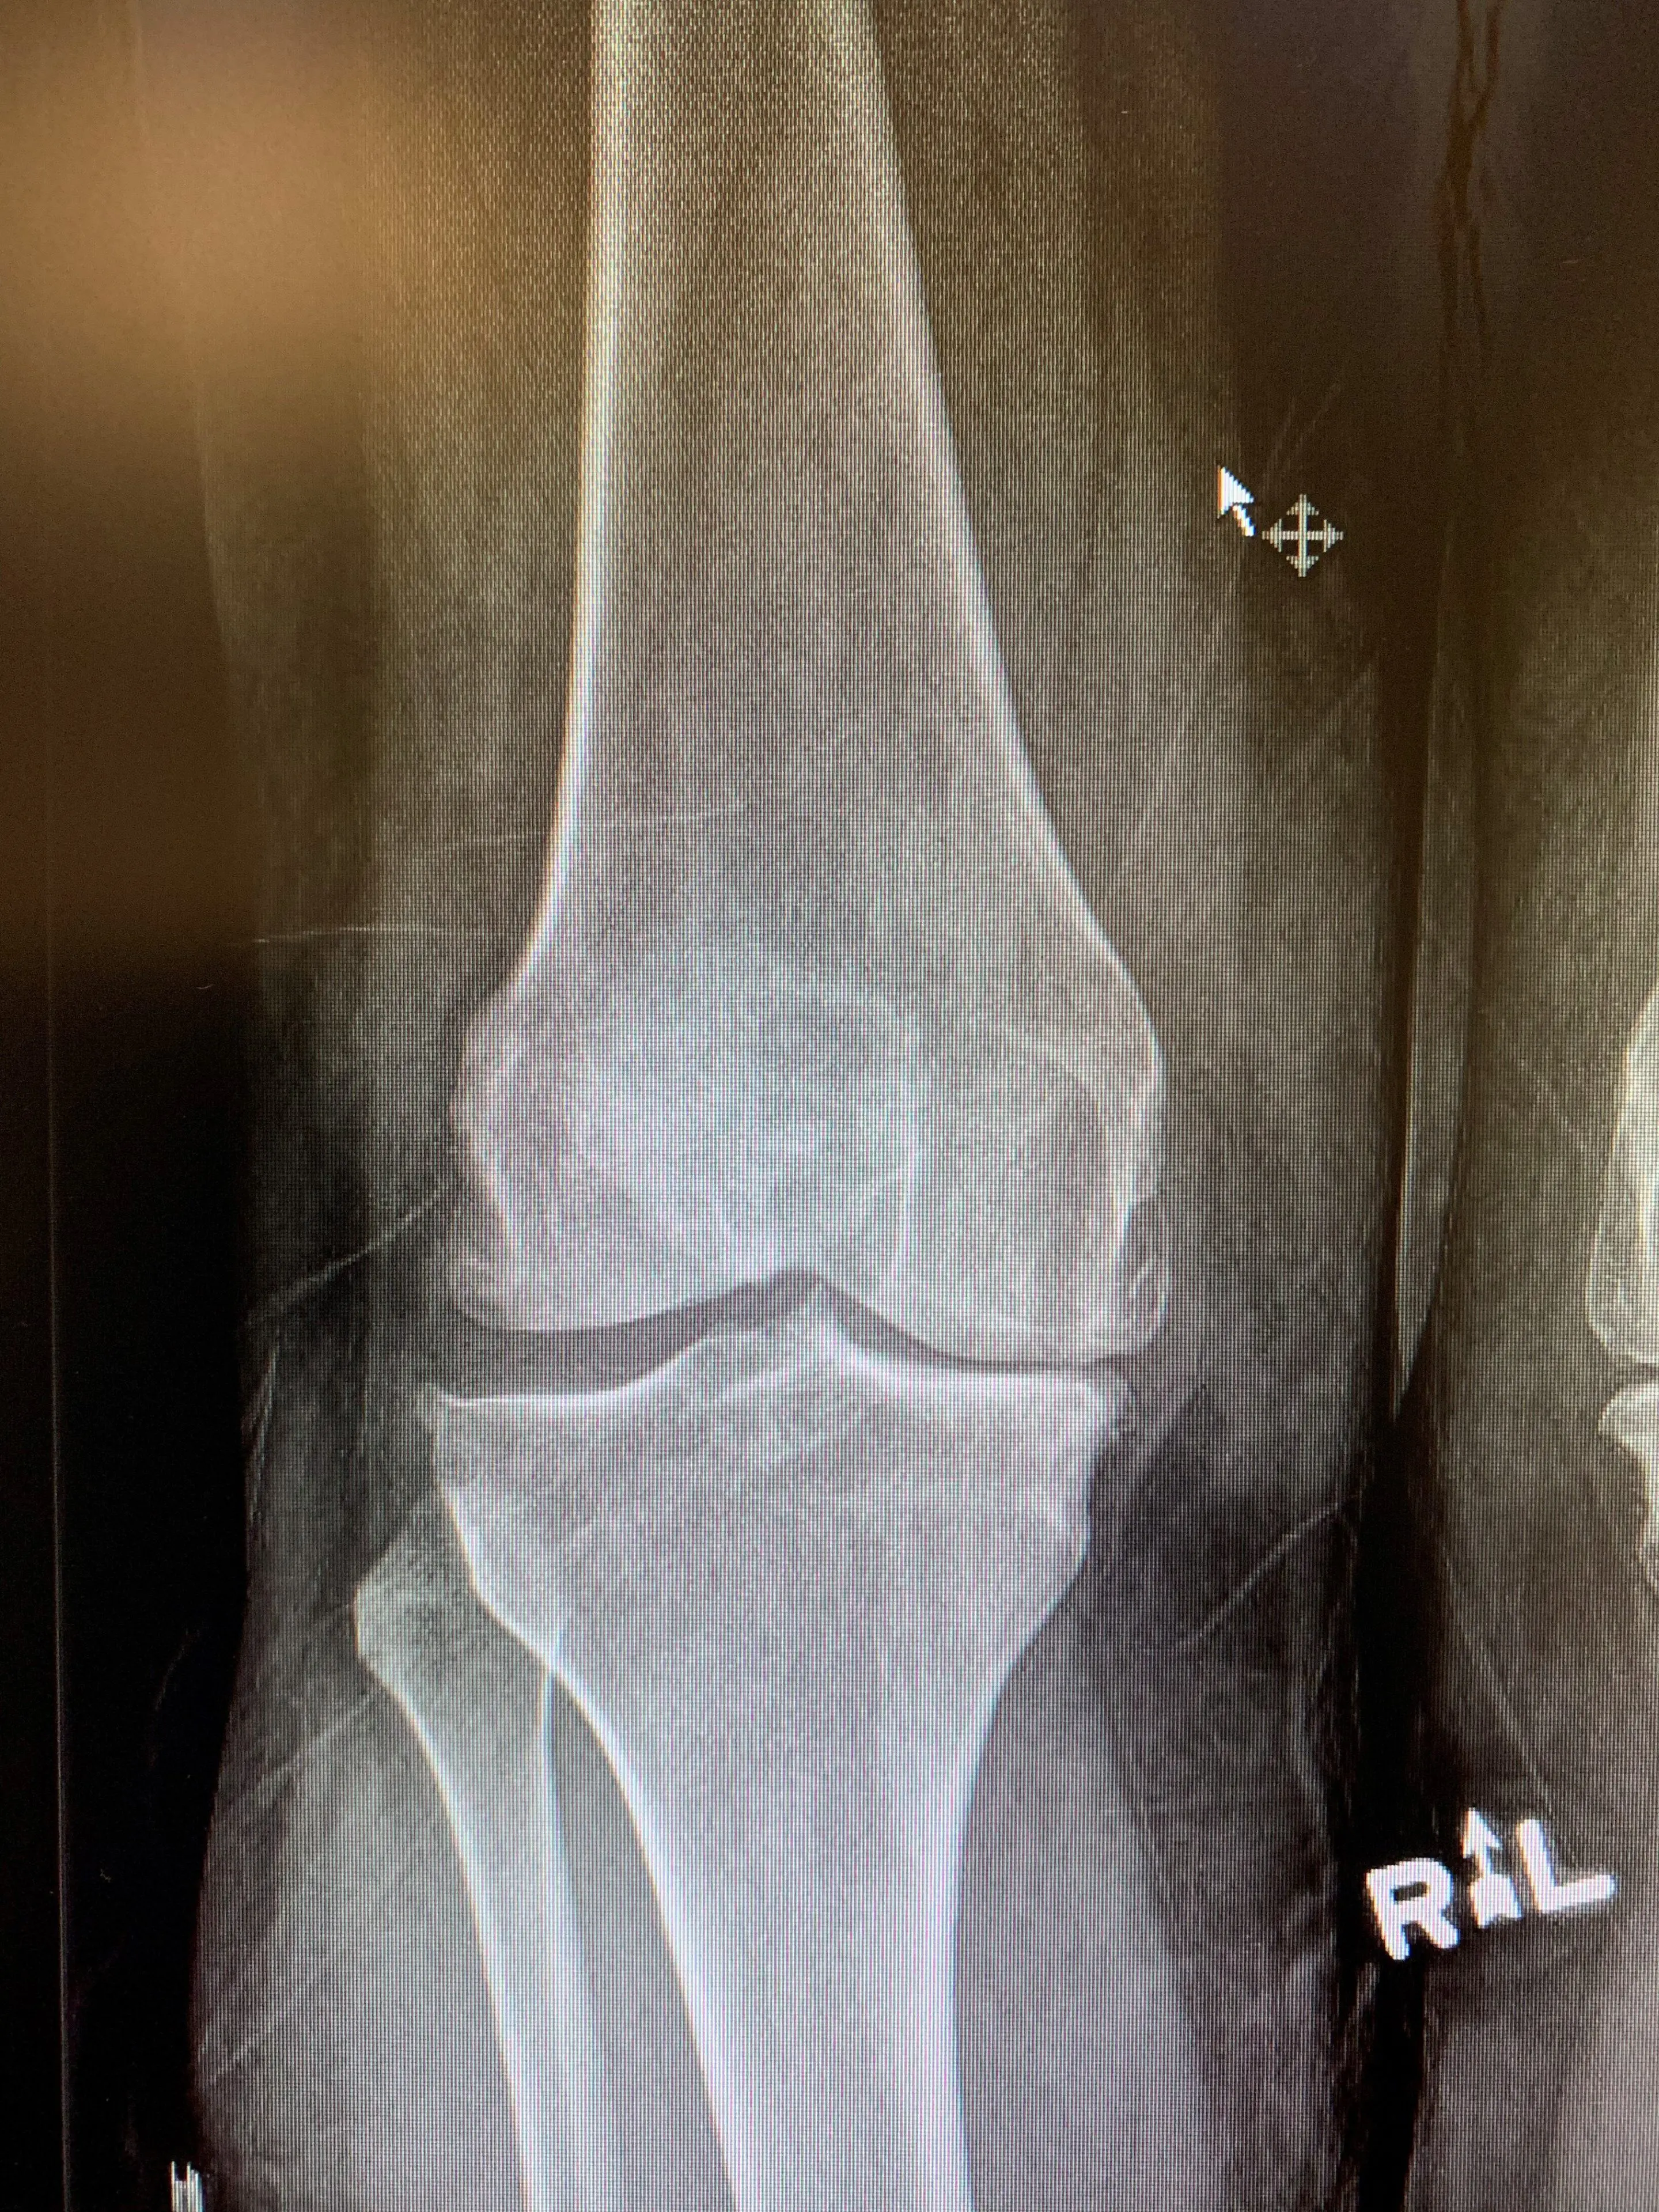

Pre opComputer navigated Primary Knee replacementa

Computer-navigated primary knee replacement.